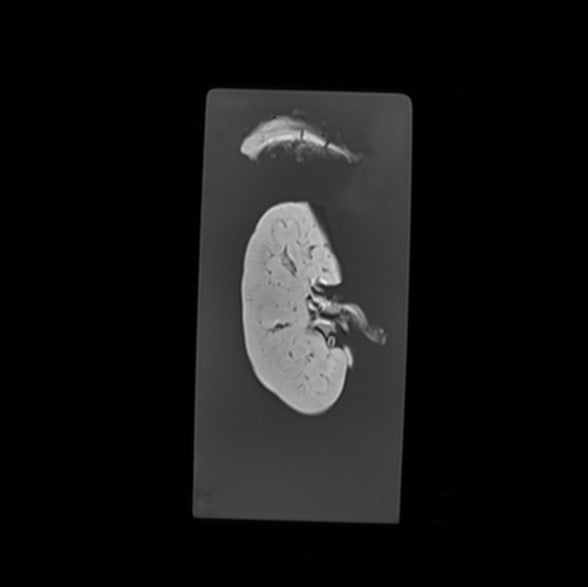

Kidney and Adrenal - Normal